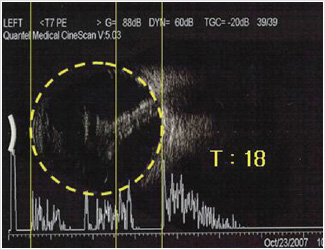

Brother Gunwi Park, 19-year-old Korean, went blind in his left eye because of atrophy of the eyeball. His sight in right eye was 0.1. After receiving Dr. Lee's prayer, he came to see things with his left eye. The intraocular pressure increased from 4 to 18, so his shrunken eyeball had returned to be normal-sized. Eyesight in his right also became 0.4.

Brother Gunwi Park's Left Eye Test Result

Before the Prayer: His eyeball was shrunken (July 18, 2006) / After the Prayer: His eyeball became normal (October 23, 2007)